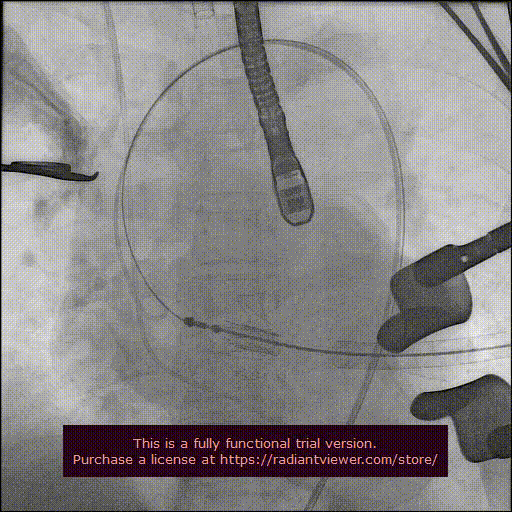

造影显示主动脉窦部

从心尖置入输送系统

定位件入窦

瓣膜降至瓣环平面

释放瓣膜

造影确认瓣膜位置

撤出输送系统

造影确认植入效果